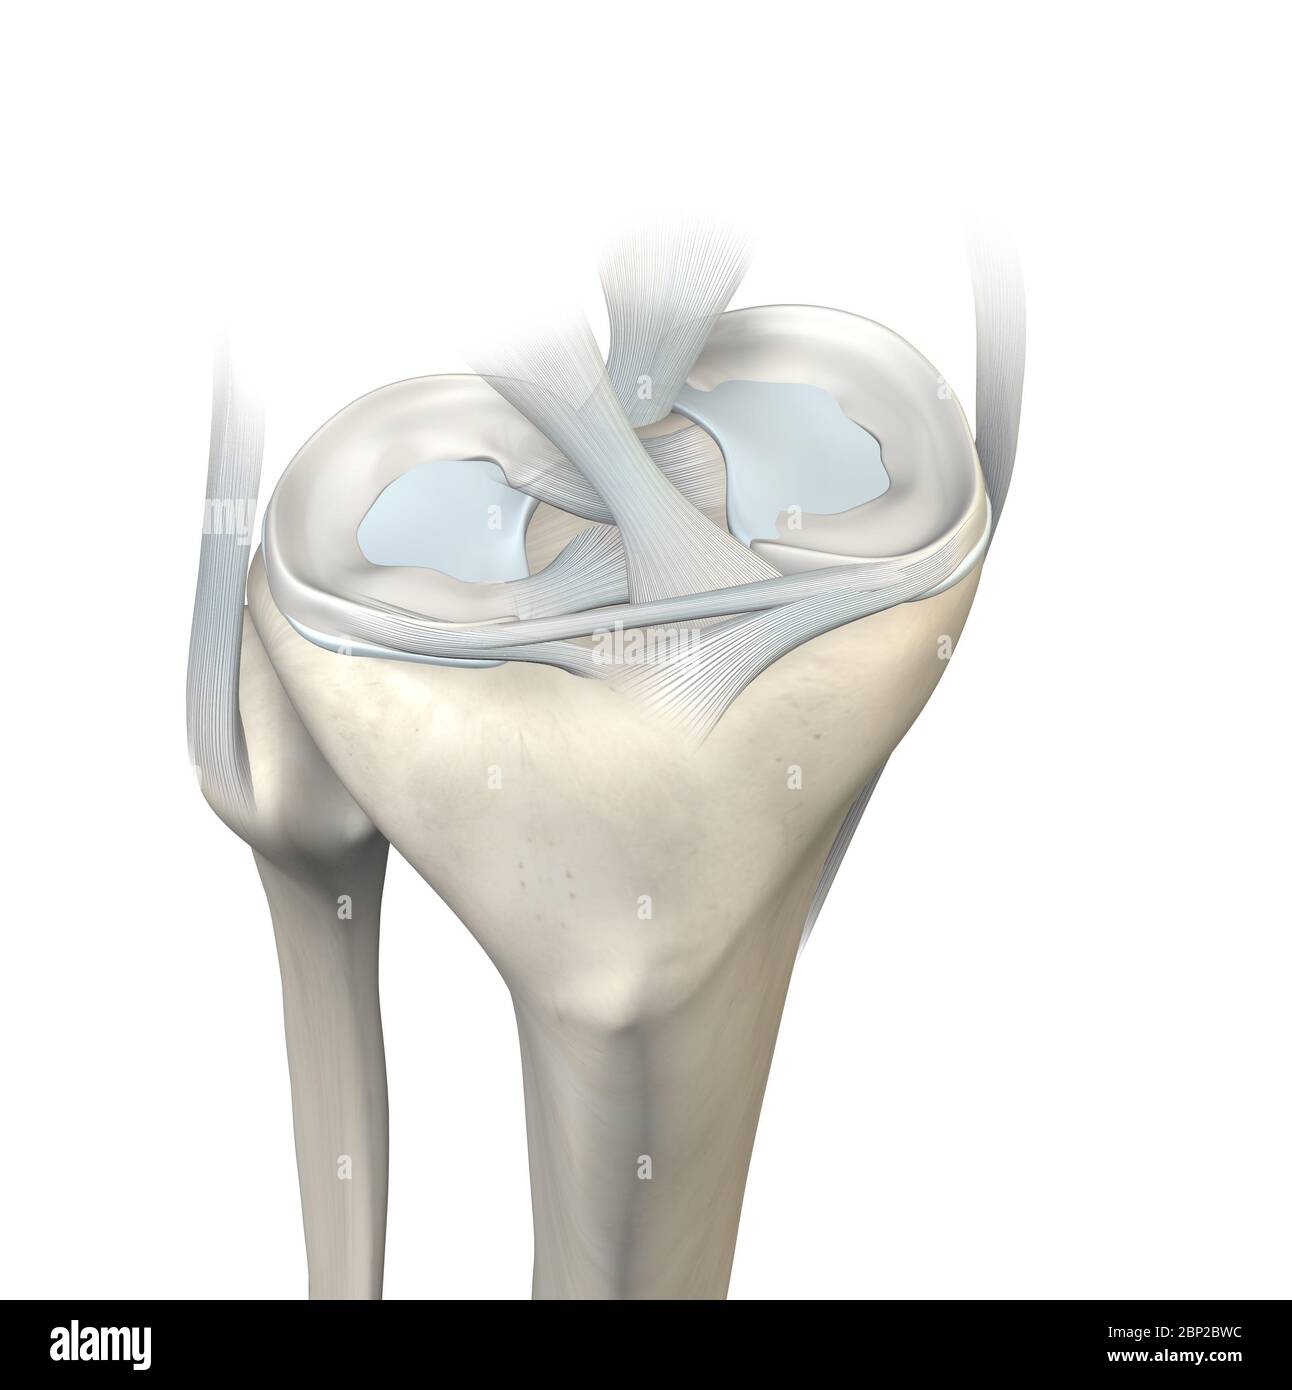

3D illustration showing knee joint with transparent femur and articular capsule, menisci and ligaments Stock Photohttps://www.alamy.com/image-license-details/?v=1https://www.alamy.com/3d-illustration-showing-knee-joint-with-transparent-femur-and-articular-capsule-menisci-and-ligaments-image357783032.html

3D illustration showing knee joint with transparent femur and articular capsule, menisci and ligaments Stock Photohttps://www.alamy.com/image-license-details/?v=1https://www.alamy.com/3d-illustration-showing-knee-joint-with-transparent-femur-and-articular-capsule-menisci-and-ligaments-image357783032.htmlRF2BP2BWC–3D illustration showing knee joint with transparent femur and articular capsule, menisci and ligaments

3D illustration showing knee joint with transparent femur and articular capsule, menisci and ligaments Stock Photohttps://www.alamy.com/image-license-details/?v=1https://www.alamy.com/3d-illustration-showing-knee-joint-with-transparent-femur-and-articular-capsule-menisci-and-ligaments-image357783041.html

3D illustration showing knee joint with transparent femur and articular capsule, menisci and ligaments Stock Photohttps://www.alamy.com/image-license-details/?v=1https://www.alamy.com/3d-illustration-showing-knee-joint-with-transparent-femur-and-articular-capsule-menisci-and-ligaments-image357783041.htmlRF2BP2BWN–3D illustration showing knee joint with transparent femur and articular capsule, menisci and ligaments

3D illustration showing knee joint with transparent femur and articular capsule, menisci and ligaments Stock Photohttps://www.alamy.com/image-license-details/?v=1https://www.alamy.com/3d-illustration-showing-knee-joint-with-transparent-femur-and-articular-capsule-menisci-and-ligaments-image357782791.html

3D illustration showing knee joint with transparent femur and articular capsule, menisci and ligaments Stock Photohttps://www.alamy.com/image-license-details/?v=1https://www.alamy.com/3d-illustration-showing-knee-joint-with-transparent-femur-and-articular-capsule-menisci-and-ligaments-image357782791.htmlRF2BP2BGR–3D illustration showing knee joint with transparent femur and articular capsule, menisci and ligaments